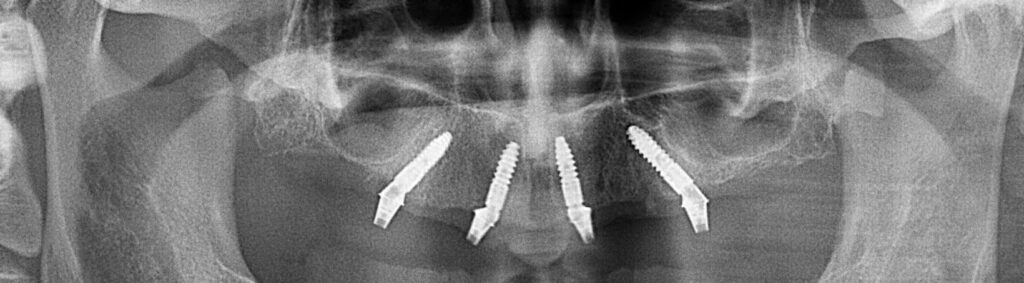

Для комплексного лікування повної адентії (відсутності зубів) використовують метод All-on-4 – вживлення 4 імплантів, на які фіксується незнімна конструкція, яка замінює всю щелепу в деяких випадках використовують ще додатково два імплантати для кращої стабільності подальшої конструкції і тоді така методика називається All-on-6-вживлення 6 імплантатів.

Це технологія яка дозволяє закріпити повній зубний ряд зубів всього на 4 або на 6 імплантатах аледуже часто з вікористанням титанової “шинуючої” фрезированої балки , і чим меньша кількість встановлених імплантатів при тотальнії реабілітації, тім вирогідність шинування імплантатів за рахунок балки вище. тому ця методика має свої плюси та мінуси та свої покази та протипокази.